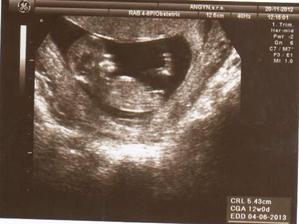

20.11.2012 - 12tt. návšteva poradne, odber krvy, USG, bábo má 5,43cm, skáče, kope....